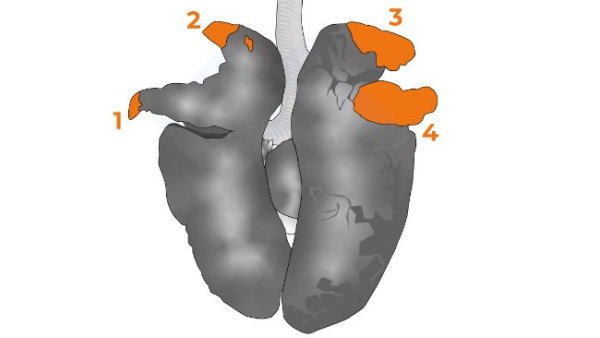

Im vierten Kapitel des Handbuchs befassen wir uns mit der Untersuchung der Organe der Brusthöhle.